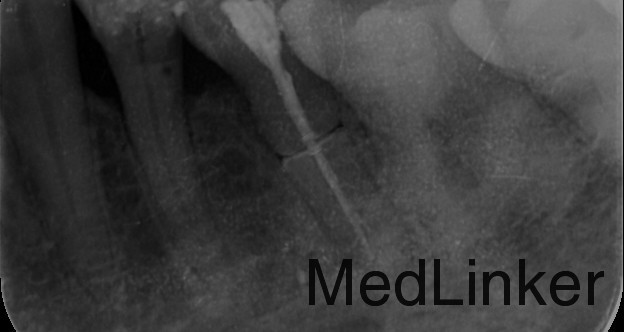

检查: 35合面见牙色充填物,探边缘密合,叩痛(+),松动I度,牙龈轻度红肿。 X线示:35根管内见致密根充影像,牙根根上、中1/3交界处连续性中断。

诊断:35根折 治疗计划:35拔除 治疗:35局部消毒,碧兰麻局部麻醉下,挺松拔除,搔刮牙槽窝,复位,局部压迫止血。常规拔牙后医嘱。 建议:修复科制定全口缺失牙修复计划